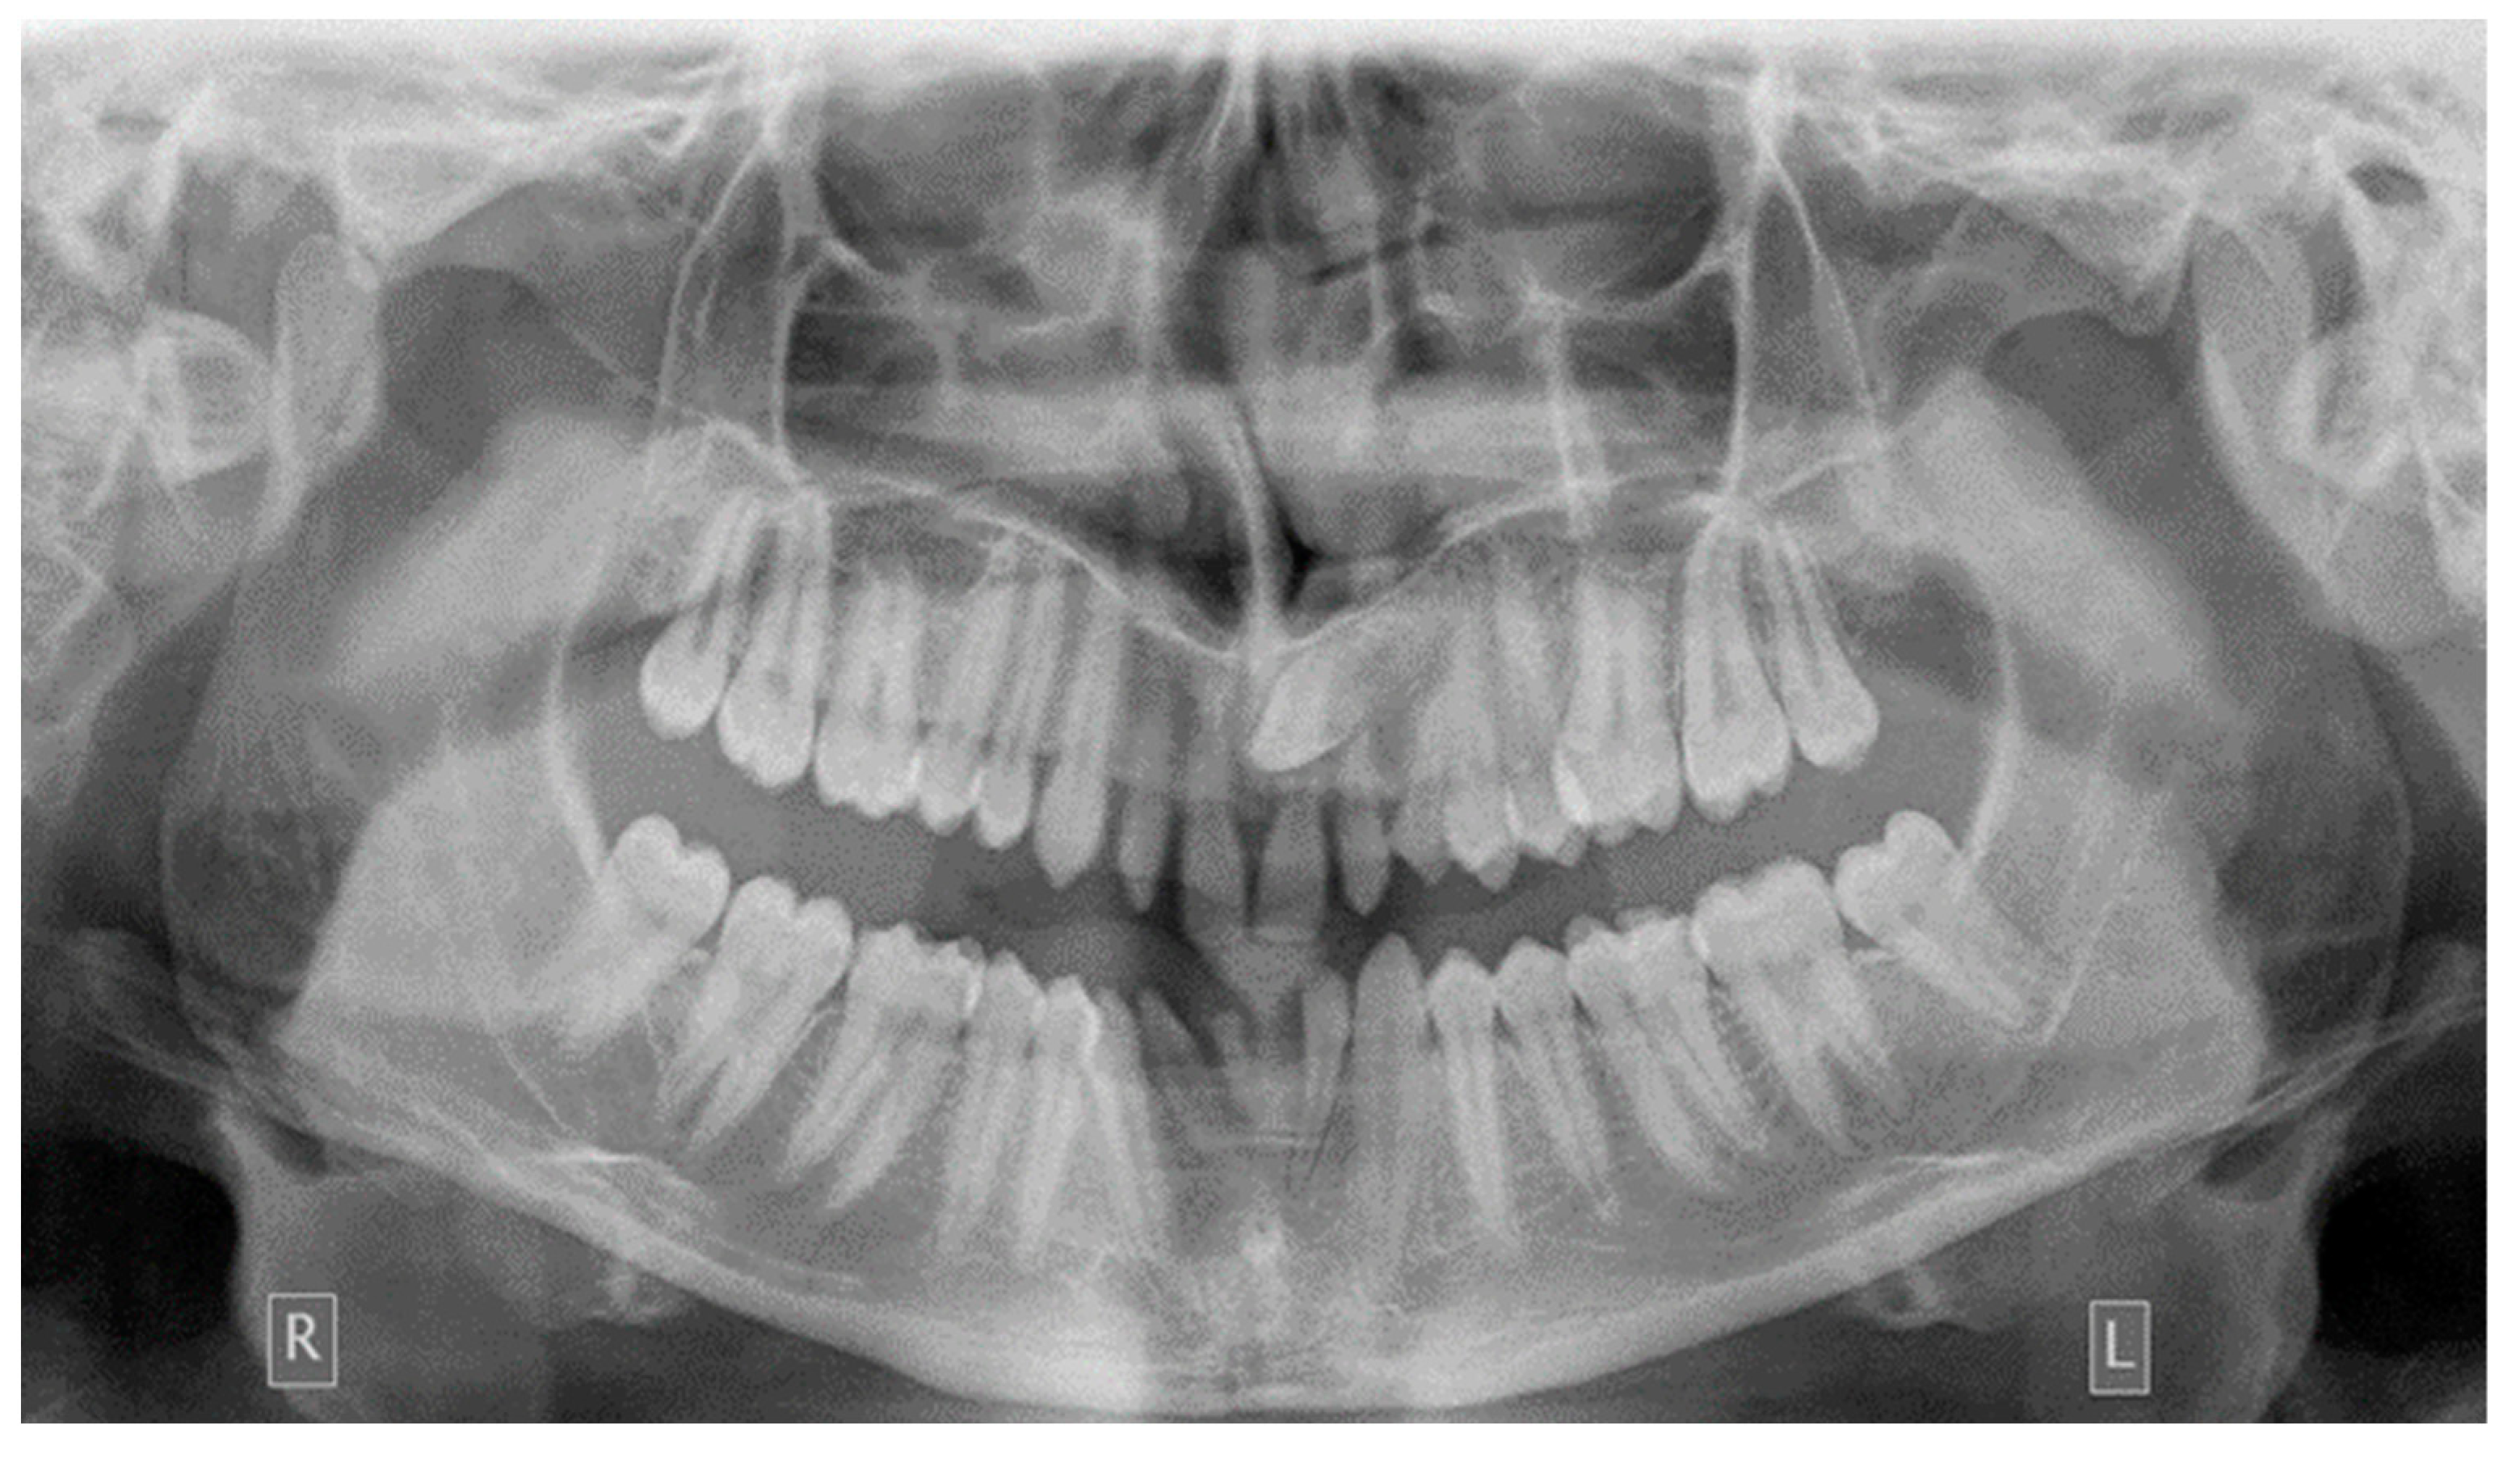

As far as the etiology of impaction is concerned, 205 patients presented one factor responsible for impaction, while 7 presented two. Table 2 shows the ectopic eruption path as the most frequent factor that was reported in 5.29% of total patients examined and mostly reported in maxillary canines. The next most common etiology was the loss of space in the arch (2.50%), followed by the ankylosis of deciduous teeth (1.71%). Concerning the rest of the causative factors, supernumerary teeth other than deciduous were observed in 1.29% of the patients, while the mesiodens was the most frequent supernumerary permanent tooth. In total, 1.21% of the sample presented tumors such as odontoma and osteoma, more often in association with maxillary central incisors. Supernumerary deciduous teeth affected 0.86% of the patients examined, while the ankylosis of permanent teeth was presented in 0.79 of the cases. The maxillary second premolars were the most frequently impacted teeth due to ankylosis. The least common etiology of impaction proved to be the primary failure of eruption, with 3 reported cases out of 212 patients, that following the radiographic examination were all confirmed by genetic tests. Panoramic radiographs indicated for some local etiological factors are presented below (Figure 1, Figure 2, Figure 3 and Figure 4).

Figure 3. Ectopic eruption of upper left canine.